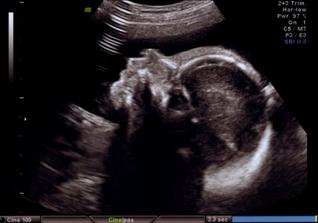

12.8.08 Dneska jsme byli i s taťkou u pana doktora. Miminko bohužel nemělo náladu a tak se k nám otočilo zádinkama.

Na ultrazvuku jsme viděli " jen " krásné zdravé srdíčko a páteř. Dostali jsme žádanku na vyšetření kvůli cukrovce. A doporučení, že nemáme jíst tolik ovoce. Prý je v něm hodně cukru a za chvilku bychom se neunesli. Tak si dáváme okurky, rajčata, papriky a tak. Ty máme taky rádi.

Ve středu 20.8.08 byla maminka s tatínkem v kině na muzikálu Mamma mia a já (malé miminko) jsem pařilo v bříšku až do rána. A na další den jsem se fotilo u pana doktora, ale o tom nic nevím, protože jsem po tak náročné noci celý den spinkalo. Alespoň si mě mohli pěkně vyfotit na 3D ultrazvuku. Změřili mi hlavičku a prý jsem se tatínkovi poved i když mě dělal po tmě

🙂.

Zatím mám takových 22 - 24 cm a vážím okolo 800 g.

Do obrazu se mi vejde už jen hlavinka.